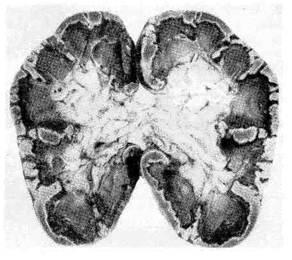

Рис. 35. Тотальный некроз коркового

вещества почки (так называемый сим-

метричный кортикальный некроз по-

чек)- Вид на разрезе.

низм лежит в основе развития некротического нефроза, симметричных некро-

зов коркового вещества (рис. 35), центролобулярных некрозов печени и т. д.